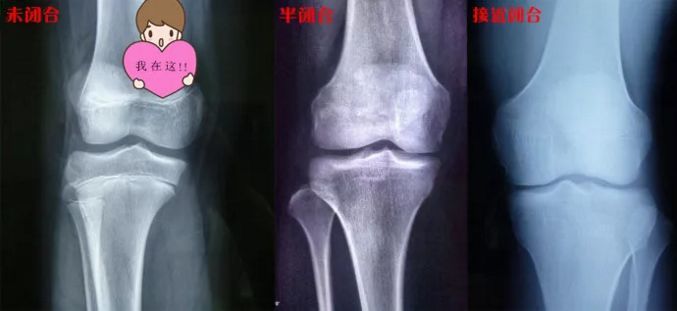

这条线就是骨骺线。

人的身高,主要是长骨的增长体现的,长骨的最终长度决定了成年后的身高。

多数情况下,只要骨骺线未闭合,就还有长高的机会;反之,当骨骺线闭合时,长骨也就不再生长了,人的身高也就基本定型了。

在骨骺线彻底闭合之前,有两个长高黄金期:3岁以内和青春期。这两个时期,骨骺线处于开启状态,长骨有足够的生长空间。